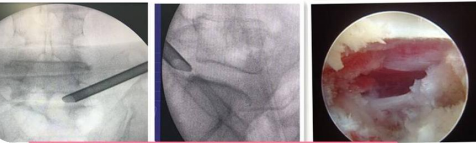

UBE(Unilateral Biportal Endscopic,单侧双通道内镜技术)

UBE(Unilateral Biportal Endscopic,单侧双通道内镜技术)是新兴的一种脊柱外科微创技术,被广泛应用于脊柱退行性疾病(包括腰椎间盘突出症、腰椎滑脱、腰椎管狭窄、颈椎病等)的治疗,收到了较好的临床效果。UBE手术具有视野清晰、创伤小、出血少、效率高、疗效好及恢复快的特点。我院在重庆市较早开展此项技术,多次通过手术直播、学术讲座和实操培训形式充分展示此项技术。

94f27ffa5ca14b1f82cb4ee9d26b4a66.Png